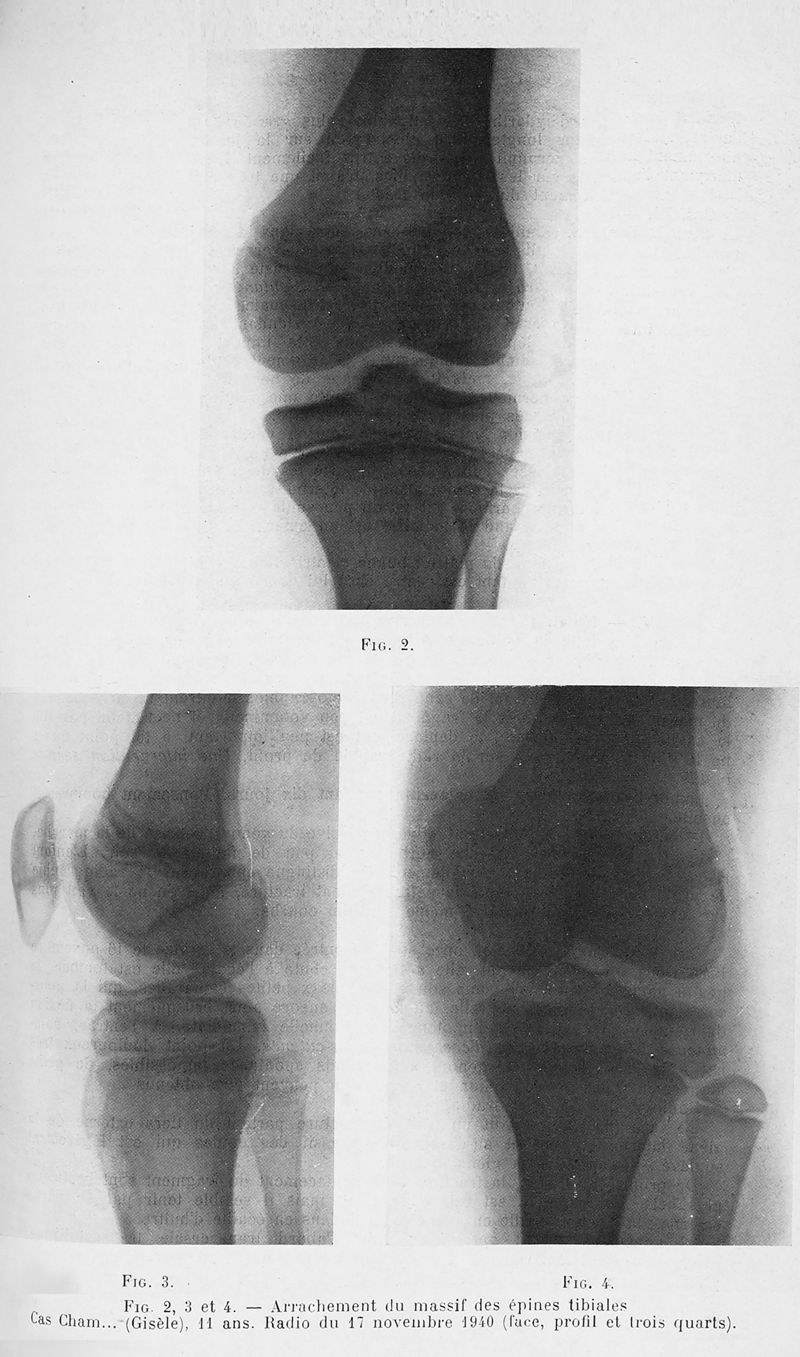

Tome 67, 1941. - Paris : Masson, 1941.